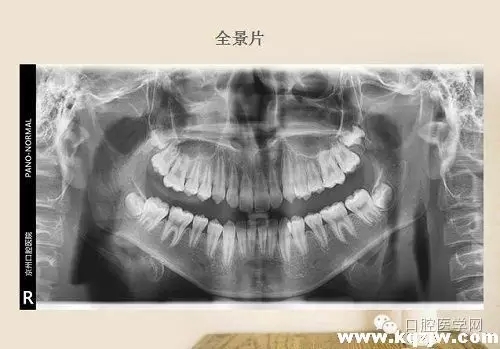

高角骨性三類錯(cuò)頜一例